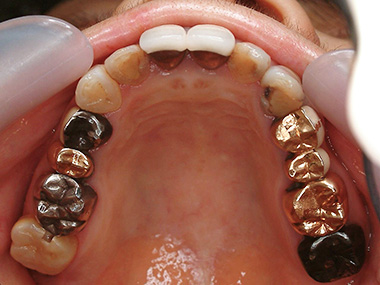

術前 開口 全体像

銀歯を綺麗にしたいとのことで来院

術前 上顎

左上4〜6番(写真右手)はブリッジからメタルボンドに変更。 5番をインプラントにします。

右上5・6番(写真左手)はメタルボンド、左右7番はゴールドクラウンに変更します。

術後 上顎

術前 下顎

左右6・7番をメタルボンド、左下5番(写真右手)をセラミックインレーにします。

術後 下顎